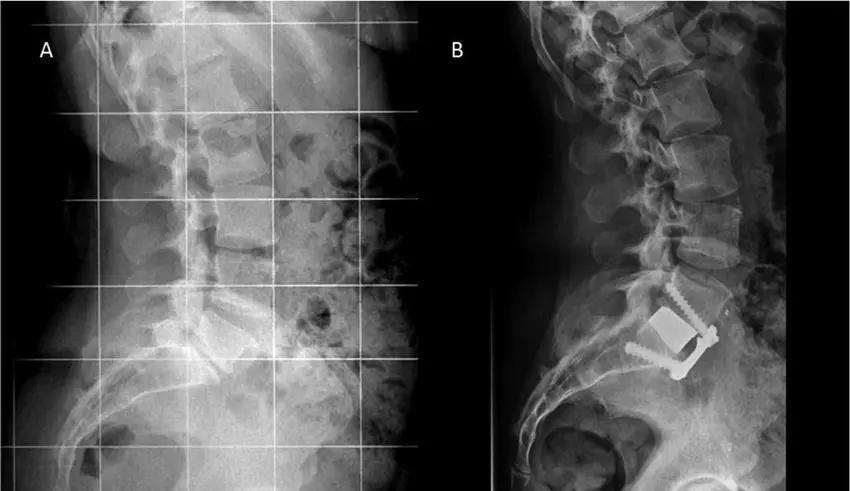

What is Vertebroplasty?Vertebroplasty is a minimally invasive spine procedure used to treat painful vertebral compressionfractures, most commonly caused by osteoporosis, trauma, or spinal tumors. In this procedure, aspecial medical bone cement is injected into the fractured vertebra to stabilize the bone andrelieve pain.The procedure is performed using image-guided techniques such as fluoroscopic X-ray guidance,allowing precise placement of the cement into the vertebral body. Vertebroplasty is widely usedto provide rapid pain relief and restore spinal stability in patients with compression fractures.SEO Keywords: Vertebroplasty Treatment, Spine Compression Fracture Treatment, MinimallyInvasive Spine Procedure, Spine SpecialistConditions Treated with VertebroplastyVertebroplasty is commonly recommended for patients with:• Osteoporotic vertebral compression fractures• Painful spinal fractures not responding to conservative treatment• Vertebral fractures due to trauma• Pathological fractures caused by tumors or metastasis• Persistent back pain due to vertebral collapseThis procedure helps stabilize the fractured vertebra and reduce severe back pain.1. The patient is positioned carefully on the operating table.2. A small needle is inserted into the fractured vertebra through the skin.3. Using real-time fluoroscopic X-ray guidance, the surgeon advances the needle into thevertebral body.4. A special bone cement is injected into the fractured vertebra.5. The cement hardens quickly, stabilizing the bone and relieving pain.The entire procedure is minimally invasive and typically requires only a small skin puncture.Advantages of VertebroplastyVertebroplasty offers several important benefits:• Rapid relief from severe back pain• Stabilization of the fractured vertebra• Minimally invasive procedure with very small incision• Short hospital stay• Faster recovery compared to open spine surgeryMany patients experience significant pain relief within 24–48 hours after the procedure.Role of X-Ray and ImagingImaging plays a critical role in vertebroplasty procedures.• X-rays and MRI scans help identify vertebral compression fractures and assess fracture severity.• Fluoroscopic real-time X-ray guidance ensures accurate needle placement during cementinjection.• Post-procedure X-ray radiographs confirm proper distribution of bone cement within thevertebral body.These imaging techniques ensure precision and safety during the procedure.Recovery After VertebroplastyRecovery after vertebroplasty is usually very quick compared to traditional spine surgery.Most patients can:• Walk within a few hours after the procedure• Return home on the same day or the next day• Resume light daily activities within a few days• Gradually return to normal activities with guided physiotherapyRehabilitation focuses on strengthening spinal muscles and preventing future fractures, especiallyin patients with osteoporosis.